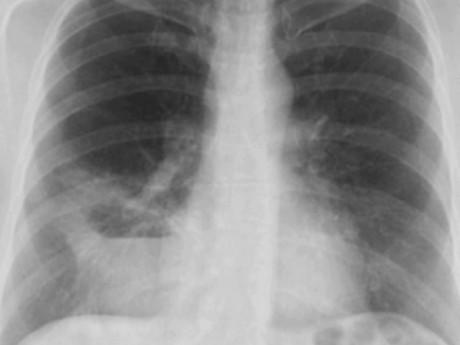

Bác sĩ Hùng cho hay, bệnh nhân Hiền tới Trung tâm điều trị không phải do bị mắc ung thư cổ tử cung mà có triệu chứng ho nhiều, đau ngực. Qua thăm khám và phim chụp CT scanner lồng ngực đã xác định chị Hiều có khối u tại phổi.

Về vấn đề logic trên lâm sàng, các bác sĩ tại Trung tâm nghĩ nhiều tới ung thư cổ tử cung di căn phổi. Nhưng khi sinh thiết tại tử cung và phổi thì là hai loại ung thư khác nhau.

Lần điều trị này bệnh nhân Hiền đã tin tưởng hoàn toàn và nghe theo theo mọi chỉ định của bác sĩ. Bệnh nhân được kết hợp nhiều phương pháp điều trị và dùng thuốc. Sau 2 năm điều trị bệnh nhân đã kiểm soát được bệnh ung thư, khối u phổi từ 7cm, hiện tan hết, không còn tổn thương ở cổ tử cung.